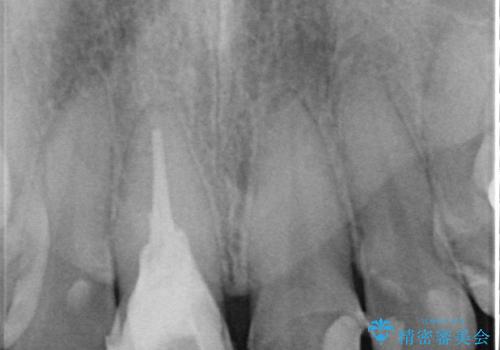

精密検査の結果、右上中切歯には**フェルール(歯の周囲の健全な歯質)**がほぼ存在せず、このままの状態での保存は困難と判断しました。

■保存治療の選択肢として**挺出(エクストリュージョン)**により歯を引っ張り出し、フェルールを確保する方法も検討可能でしたが、患者様のご希望により、より短期間で審美性を回復できる治療法を選択。

▶右上中切歯

抜歯後、即時インプラント埋入

審美性を考慮し、仮歯を即日装着

治療期間を最小限に抑えつつ、自然な前歯のラインと歯ぐきの形を維持